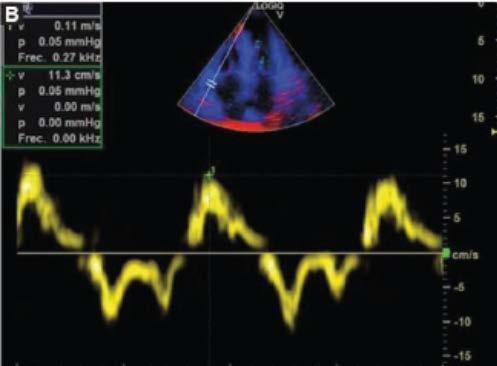

1. Evoluciona con clínica tórpida, desarrollando signos de IC por lo que se solicita electrocardiograma (Fig. 1), ecocardiograma Doppler color (Fig. 2) y resonancia magnética nuclear cardiaca. Esta última informa: ventrículo izquierdo no dilatado, leve incremento de espesor parietal septal (12 mm), fracción de eyección de ventrículo izquierdo: 51%. IM leve, AI moderadamente dilatada. Fibrosis difusa transmural inferoseptal basal e inferoseptal medial, fibrosis subendocárdica en pared inferior de ventrículo derecho. Valores de T1 mapping nativo aumentados en forma difusa (valores mayores a 1110 ms). Volumen extracelular (VEC) 55%, hallazgos compatibles con AC. Por referir palpitaciones se solicita estudio holter de 24 horas (Fig. 3).

Se diagnostica mieloma múltiple y AC con IC función sistólica preservada, iniciando tratamiento dirigido a ambas enfermedades. En su seguimiento presenta mejoría clínica de la función renal y cardiaca; luego de dos meses de tratamiento, las mediciones de NT-pro BNP y troponina I ultrasensible habían descendido un 30%. En ecocardiograma control se puede objetivar mejoría de la función diastólica, progresando desde una disfunción diastólica III (flujo transmitral tipo restrictivo) a una tipo I (flujo transmitral prolongado), mejoría en Doppler tisular y parámetros de deformación longitudinal global.

B

D

Figura 2. Ecocardiograma Doppler color. A: paraesternal 4 cámaras, hipertrofia concéntrica. B: deterioro de la función sistólica de ventrículo derecho evaluada por Doppler tisular. C: relación Doppler de flujo transmitral y Doppler tisular mitral lateral alterado. D: disfunción diastólica grado III. A

C

Ecocardiograma

Lo característico de esta enfermedad es que el infiltrado afecta aurículas y tabique interauricular, aumento simétrico del espesor parietal ventricular derecho e izquierdo con un aspecto brillante moteado tipo granular y sistema de conducción. Los cambios para comenzar a considerar el diagnóstico diferencial de AC son la relación Ee´ > 9.6, el volumen auricular izquierdo indexado y la disminución en la fracción de contractilidad miocárdica o fracción de acortamiento. Además, entre otros parámetros habituales pueden citarse el índice de excentricidad o espesor parietal relativo, ―ya que el fenotipo habitual en los pacientes con AC es de hipertrofia ventricular izquierda (HVI) concéntrica―, y el engrosamiento difuso valvar13.

Inicialmente, disminuye la complacencia auricular y aumenta la presión intraauricular, lo que lleva a que se ocupe menor tiempo tanto en el llenado ventricular como en el auricular. El descenso del llenado diastólico precoz es compensado por un enérgico llenado diastólico final, lo que, en estadios avanzados de la enfermedad, se traduce en una pseudonormalizacion del patrón. Por otro lado, otros autores han observado que la progresión de la enfermedad conlleva deterioro precoz de la diástole, pero no puede diferenciarse si este cambio se debe al envejecimiento normal celular. Es decir, que pueden observarse un patrón transmitral tipo pseudonormal, más habitual, o un patrón prolongado, el cual deberá diferenciarse de los cambios producidos por el envejecimiento. Otro aspecto a considerar es la afectación de la válvula mitral, ya que se ha observado una alta prevalencia de insuficiencia mitral que altera el patrón de llenado ventricular. Conforme avanza la enfermedad también se observan cambios en el patrón de las venas pulmonares. La evaluación de la función diastólica se correlaciona con la gravedad de la enfermedad y puede ser utilizada en su seguimiento14,15.